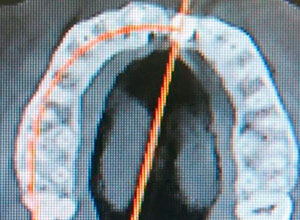

Se realizó distracción alveolar vertical histogénica, incluyendo el implante. La mecánica de la distracción usada en este caso en especial es la tracción elástica y/o alámbrica mediante brackets de ortodoncia.

Decidimos hacer una corticotomia alveolar, dejando tejidos blandos en su lugar y cambiar la corona de cerámica por una corona de acrílico para cementar bien los brackets y poder empezar con la distracción.

Se empezó a hacer la distracción, primero con un arco recto y posteriormente con elásticos haciendo el recorte con el borde incisal conforme se va bajando el implante con el bloque óseo.